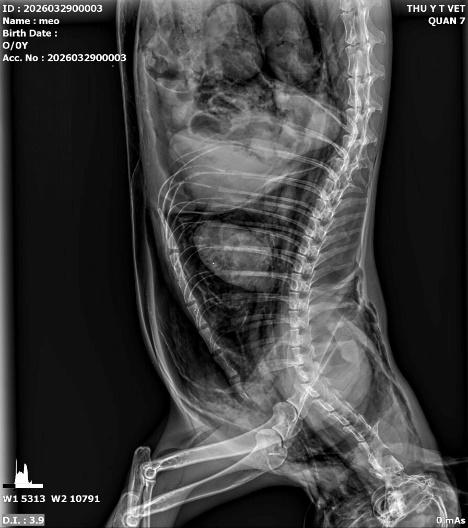

Tình trạng táo bón kinh niên dẫn đến giãn đại tràng (Megacolon) rất thường gặp ở mèo già hoặc mèo ăn quá nhiều xương nhưng ít uống nước. Trên phim X-quang, bác sĩ sẽ thấy hình ảnh đại tràng giãn lớn, chứa đầy khối phân nén chặt, khô cứng. Nếu không giải quyết kịp thời, độc tố từ phân sẽ thấm ngược vào máu gây nhiễm độc cơ thể. Chụp X-quang giúp chúng tôi đánh giá mức độ nghiêm trọng để có phương án thụt tháo hoặc phẫu thuật cắt bỏ đoạn đại tràng bị giãn.

.jpeg)

Hình ảnh: tắc phân trên bé mèo